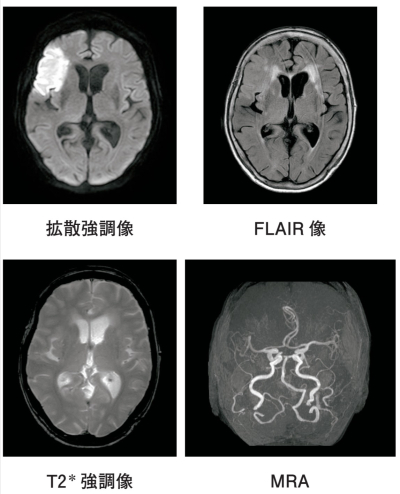

血液生化学検査に異常を認めない。午前8時に撮像した頭部MRIの拡散強調像、FLAIR像、T2*強調像、MRAを別に示す。